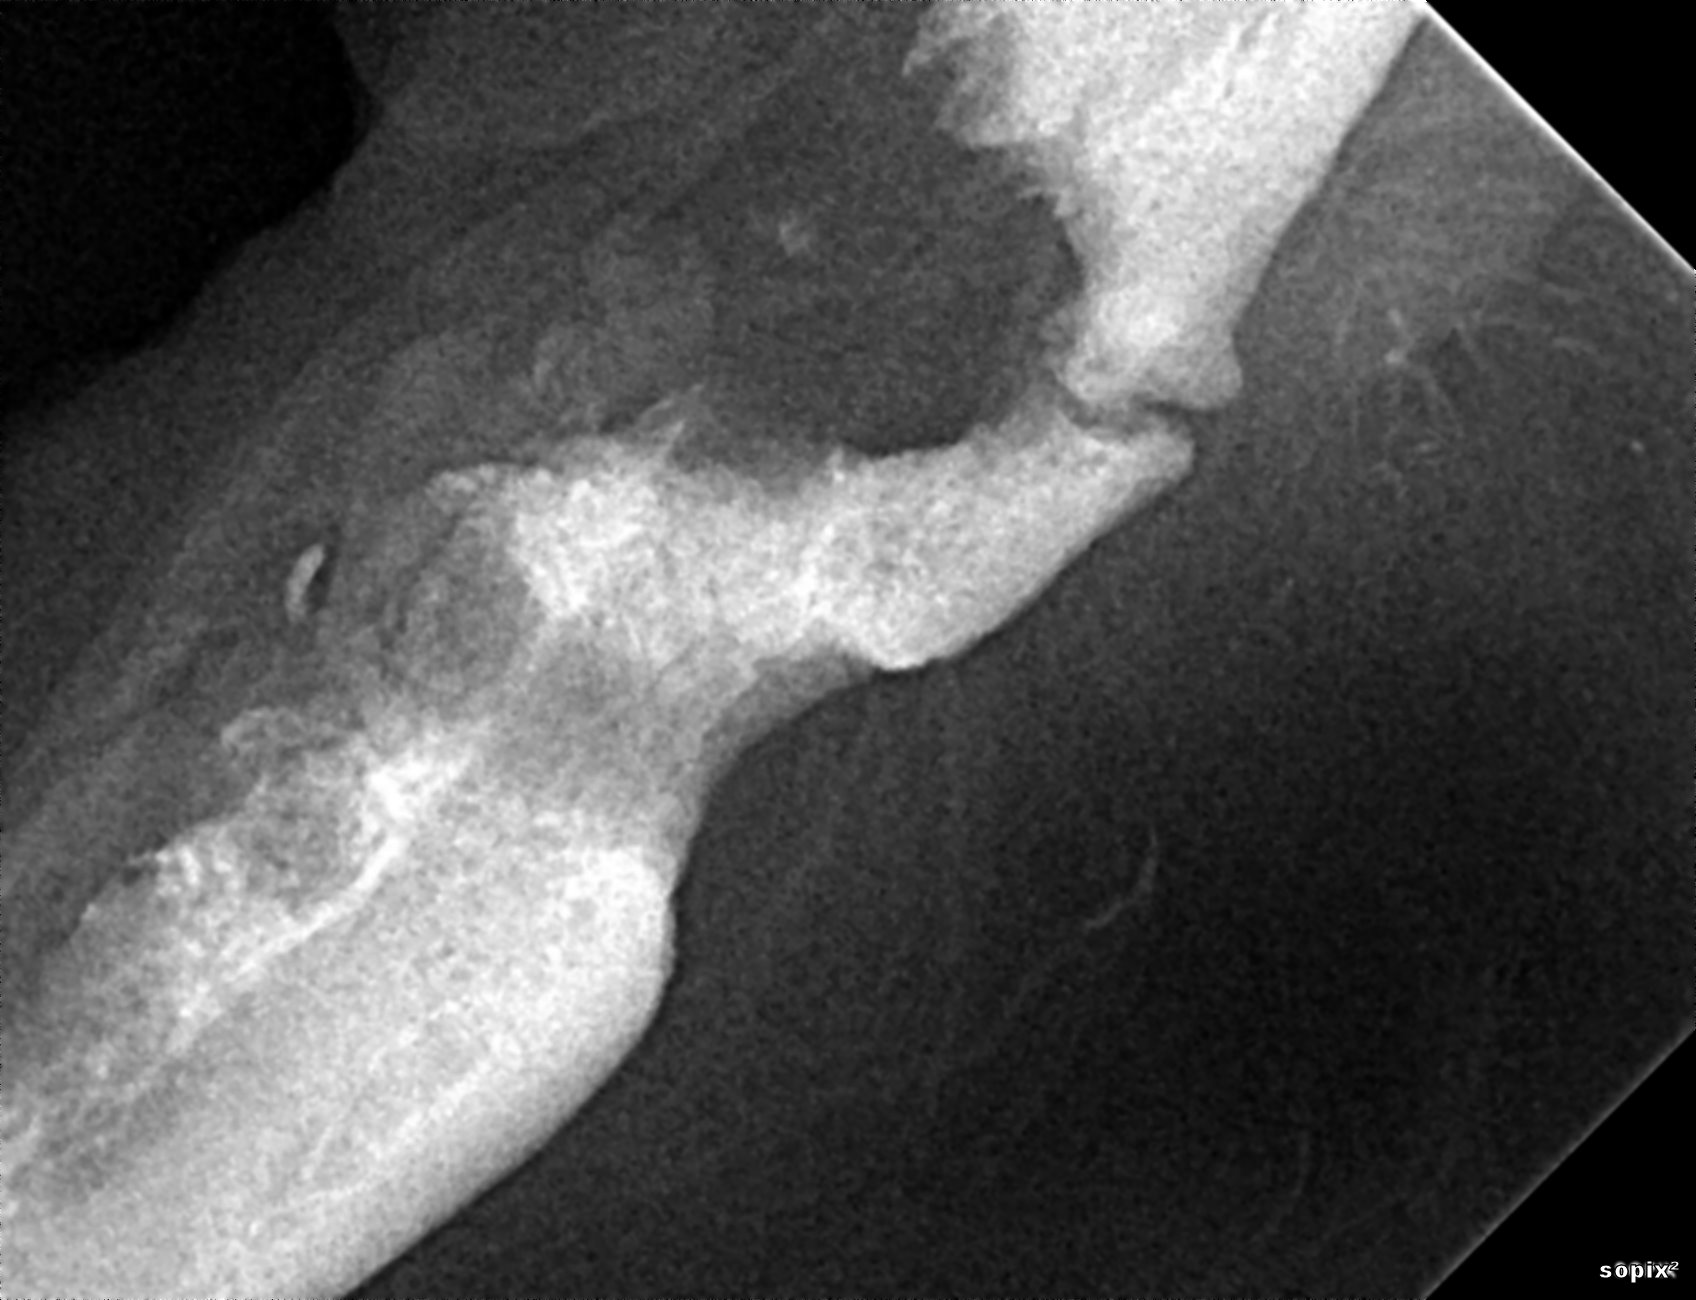

De même, la perte d’os autour des canines et prémolaires peut provoquer une communication oro-nasale (la zone la plus classiquement touchée est la face palatine des canines chez les petits chiens à museau long et fin : Teckel, Caniche…). La gestion de ces communications oro-nasales d’origine parodontale nécessitent les extractions des dents atteintes, le curetage des alvéoles dentaires, de la cavité nasale et la fermeture des sites par de grands lambeaux muqueux suturés sans tension à la muqueuse palatine 9. Les dégâts osseux et nasaux sont préalablement évalués par la réalisation d’un scanner (ou d’un cone beam) afin de visualiser au mieux les structures et planifier l’ampleur des extractions et du curetage (figures 3a à d).

Figure 3a : maladie parodontale avancée chez un Teckel à l’origine d’une communication oro-nasale au niveau maxillaire D.

Figure 3b : Scanner du même chien qu’en 3a au niveau de la canine (à gauche) et de la deuxième prémolaire (à droite). Une lyse osseuse péridentaire importante est notable ainsi qu’un envahissement de la cavité nasale D et des structures endonasales.